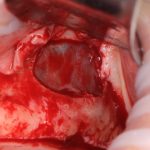

Изоляция области аутографта и имплантатов барьерной мембраной.

Перекрывать костный блок барьерной мембраной или оставить так? По этому вопросу есть много мнений. Между тем, в публикации по методике есть ясное показание, когда это требуется.

Конкретно в этом клиническом случае между костным аутотрансплантатом, ложем и имплантатами есть пустое пространство. Если его не изолировать от мягких тканей, они прорастут и осложнят интеграцию аутографта. Поэтому я решил перекрыть костный блок барьерной мембраной, пусть это делает хирургическую операцию немного дороже.

— ты знаешь, что барьерная мембрана может выполнять две функции, каркасную и изолирующую. Первая функция требует обязательной фиксации и натяжения, вторая — нет. В нашем случае «каркасом» регенерата является костный блок, а барьерная мембрана нужна только для изоляции. Поэтому она не требует натяжения и фиксации пинами.

После я внимательно проверил, что костный блок и имплантаты полностью перекрыты. Теперь рану можно ушивать.